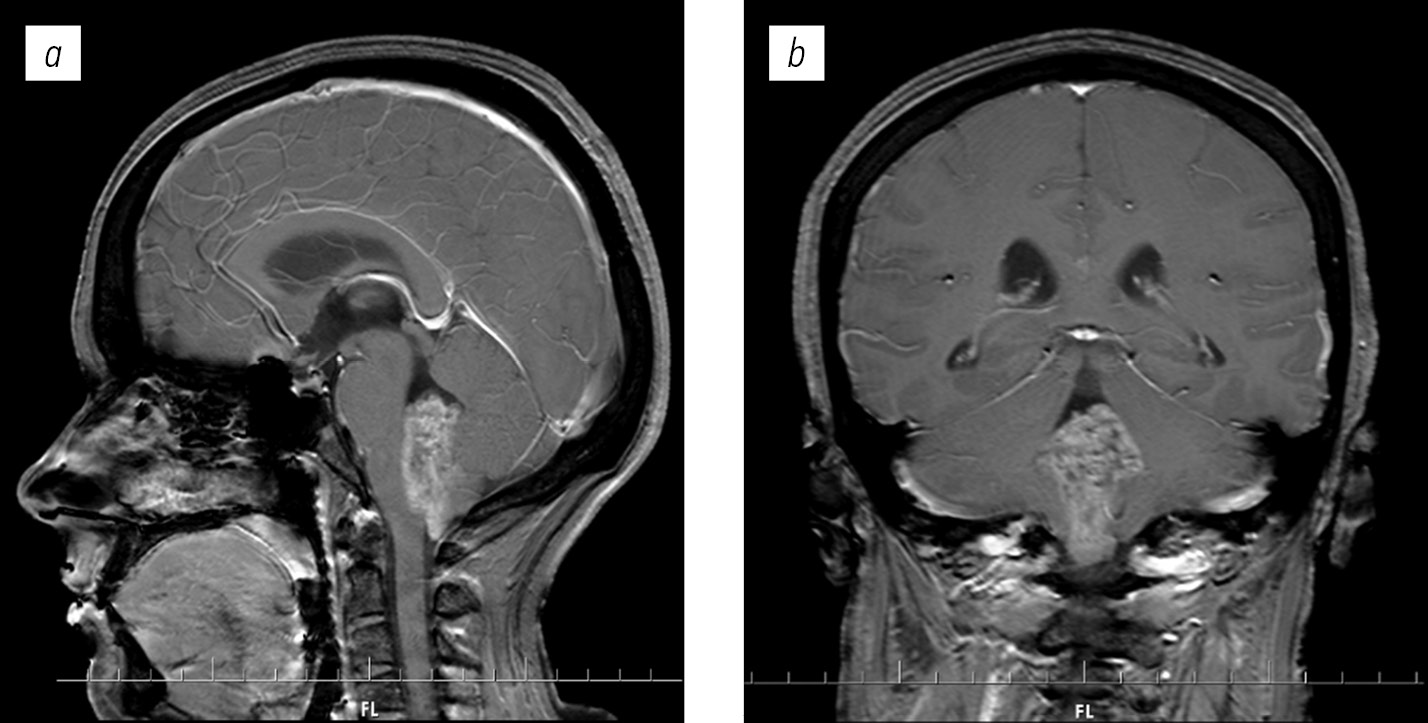

Клиническое наблюдение

Пациентка Я., 34 года, поступила в НМИЦН 19.05.2021 с диагнозом «опухоль четвертого желудочка». Из анамнеза известно, что 6 мес. назад начали беспокоить головные боли, тошнота, рвота, икота. При выполнении МРТ была диагностирована опухоль четвертого желудочка больших размеров (рис. 2). Пациентке было предложено оперативное вмешательство. По данным неврологического осмотра очаговой неврологической симптоматики не отмечено.

Рис. 2. Дооперационные магнитно-резонансные томограммы с контрастным усилением пациентки Я. в сагиттальной (а) и коронарной (b) проекциях

Fig. 2. Preoperative magnetic resonance imaging studies with contrast of the patient Y. in the sagittal (a) and coronal (b) projections